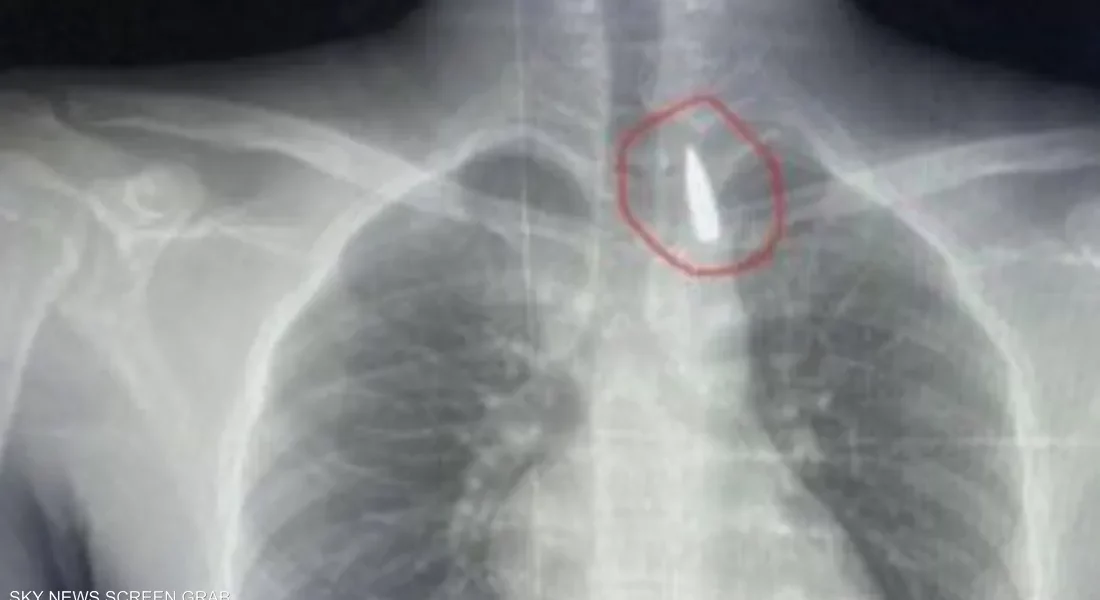

في إنجاز طبي استثنائي، نجح فريق طبي متخصص في مستشفيات جامعة الإسكندرية بمصر في إجراء عملية جراحية دقيقة لإنقاذ مصاب فلسطيني من قطاع غزة، بعد استخراج مقذوف استقر في تجويف القفص الصدري على مقربة من الشريان الأورطي.

وأوضح عميد كلية الطب ورئيس مجلس إدارة المستشفيات الجامعية في الإسكندرية، الدكتور تامر عبد الله، أن الجراحة أجريت بمشاركة فريق من أطباء جراحة القلب والصدر والتخدير والمعاونين، وتم خلالها التعامل مع حالة بالغة الخطورة نظراً لتموضع المقذوف بالقرب من أهم شرايين الجسم المسؤول عن تغذية الأعضاء الحيوية.

وأكد عبد الله أن العملية استمرت عدة ساعات داخل المستشفى الجامعي الجديد، وتمكن الأطباء خلالها من استخراج المقذوف بأمان، مشيراً إلى أن المريض يتلقى حالياً الرعاية الطبية المكثفة وحالته مستقرة وتحت المراقبة الدقيقة من الفريق المعالج.